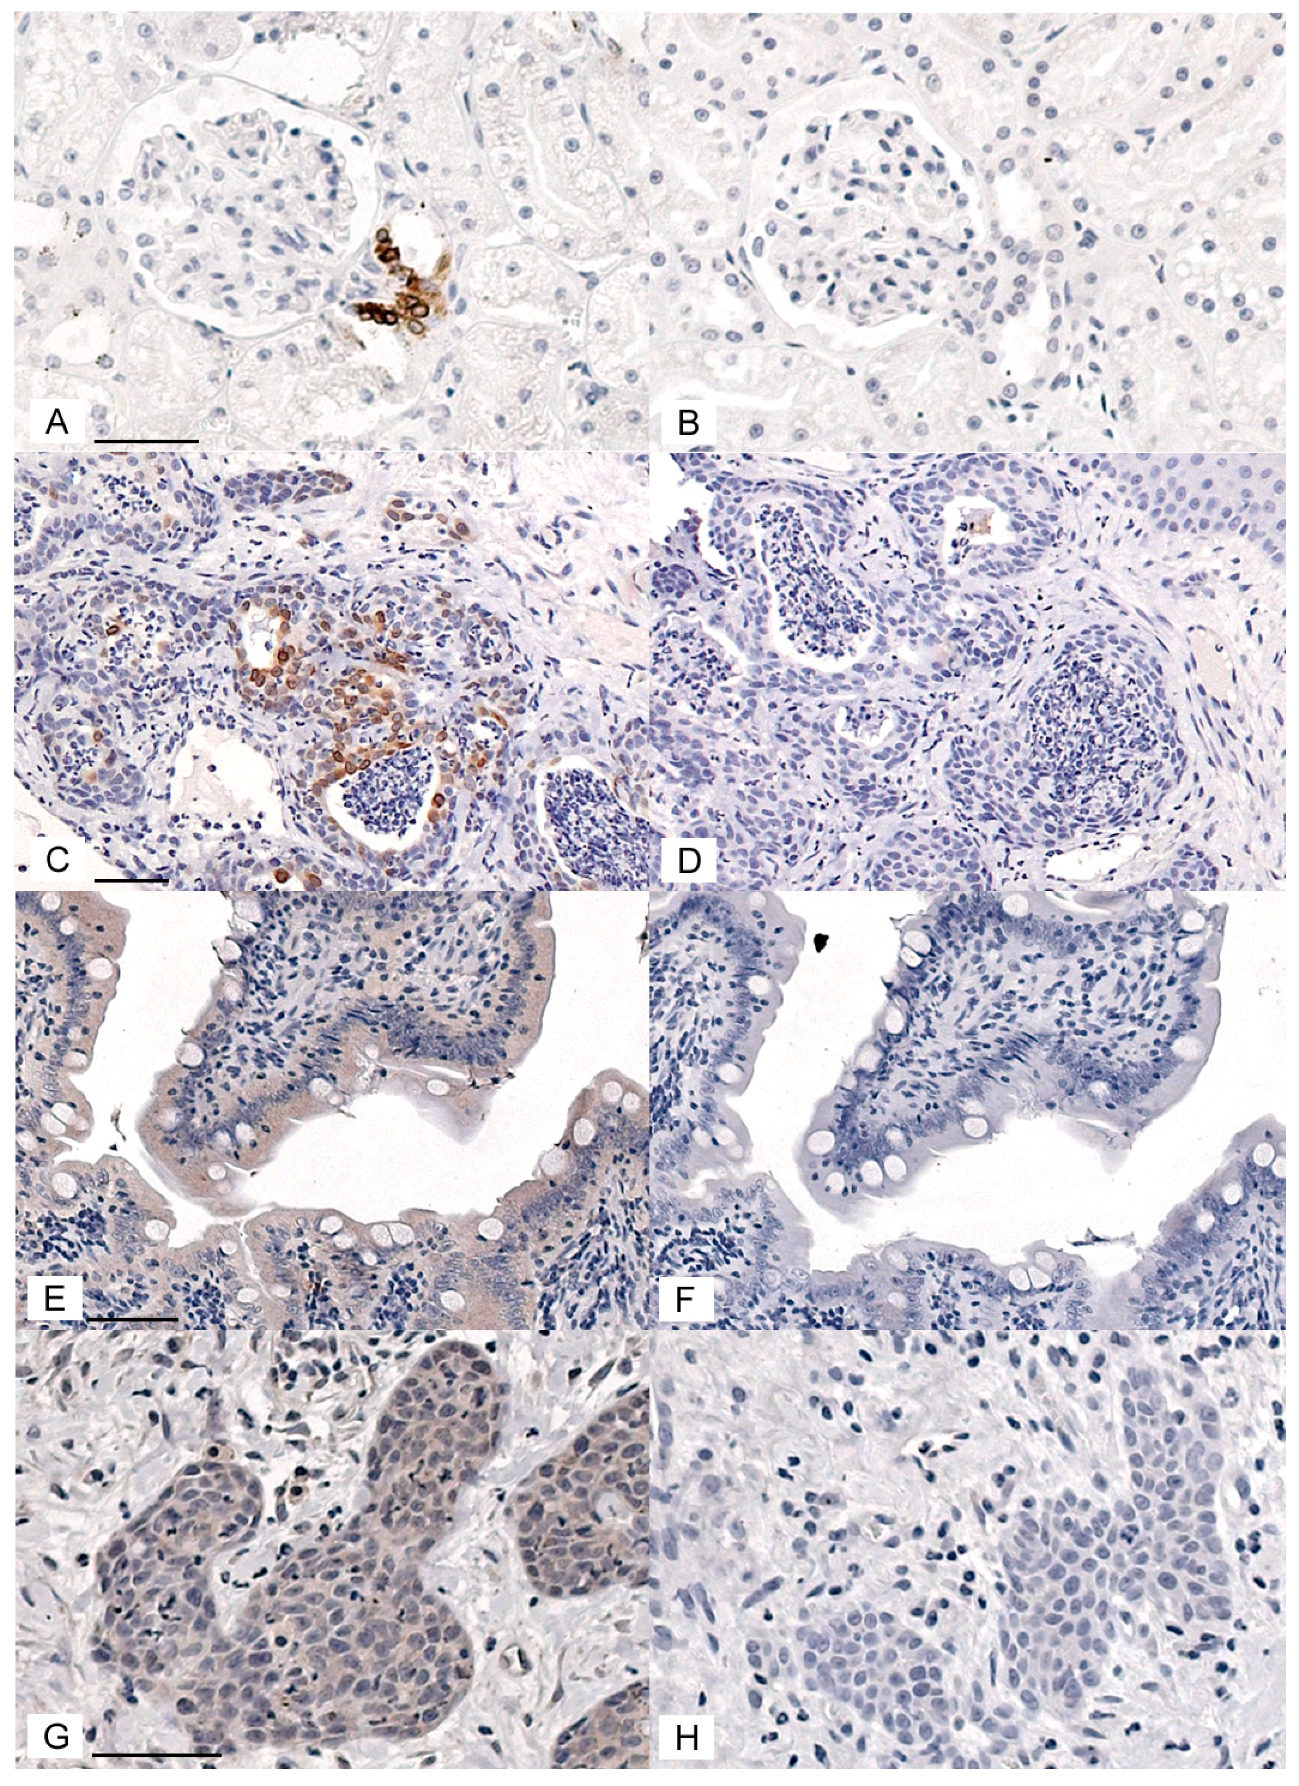

In order to evaluate COX-1, COX-2, and CD147 expression in feline OSCC, immunohistochemical protocols were developed and optimized. COX-2 immunohistochemistry gave positive signal in feline macula densa cells and in feline OSCC (Figure 1A,C). Replacing the primary antibody with control rabbit IgG eliminated the staining (Figure 1B,D), CD147 immunohistochemistry gave a positive signal in feline small intestine enterocytes, as well as feline OSCC (Figure 1E,G). Replacing the CD147 antibody with control goat IgG significantly reduced staining (Figure 1F,H). Rabbit anti-COX-1 antiserum yielded a positive signal in feline intestinal goblet cells and feline OSCC (Figure S1). Unfortunately, replacing the COX-1 antiserum with normal rabbit serum (negative control) demonstrated reduced staining in goblet cells but a high amount of nonspecific stain that was indistinguishable from the COX-1 anti-serum in feline OSCC (Figure S1). COX-1 immunohistochemistry was not selected for further analysis.

Figure 1.

COX-2 and CD147 positive and negative controls for immunohistochemistry. (A–D) Photomicrographs of IHC staining using rabbit anti-COX-2 IgG (1:200) and normal rabbit IgG (1:200, negative control). The chromogen is DAB (brown), and the counterstain is hematoxylin (blue). The feline renal macula densa epithelial cells had an intense cytoplasmic signal (A) that was eliminated when the antibody was replaced with normal IgG (B). Scattered oral squamous cell carcinoma (OSCC) cells showed an intense cytoplasmic COX-2 signal (C), which was eliminated when the primary antibody was replaced with normal IgG (D). (E,F) IHC staining using goat anti-CD147 IgG (1:100) and normal goat IgG (1:100, negative control). Feline enterocytes showed moderately intense cytoplasmic and membranous signal (E), which was markedly reduced when the primary antibody was replaced with normal goat IgG (F). There was widespread moderate staining and scattered heavy staining of OSCC cells (cytoplasm and membrane), and light to moderate widespread staining of stromal cells (G). Staining was markedly reduced when the primary antibody was replaced with normal goat IgG (H). Each pair of positive and negative control images are at the same magnification. Scale bars are 50 μM long.